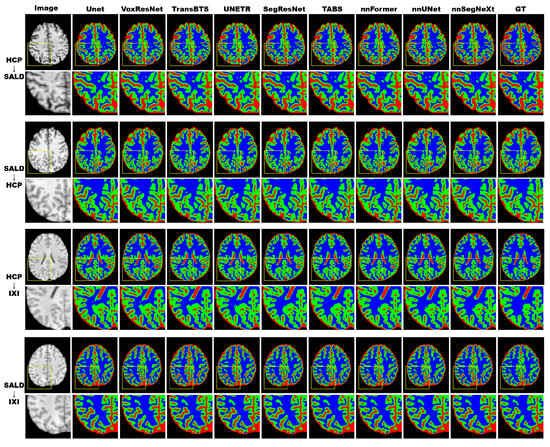

3.4.2. Model Generality